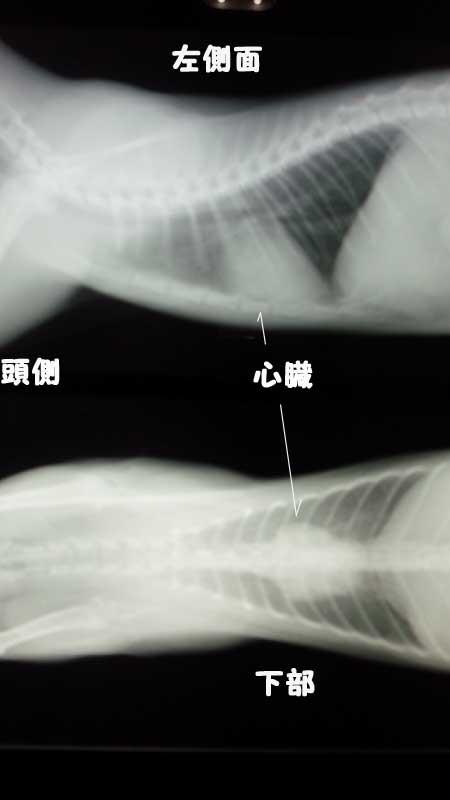

これは、セナちゃんが避妊手術の時に撮影したレントゲンです。

心臓の形がハート型ポイ感じです。

心臓がハート型になるとバレンタインハートと言って「猫の肥大型心筋症」の疑いがあります。

この時はまだ子猫でしたのハッキリした事が解らないとのことで半年後に再検査となりました。